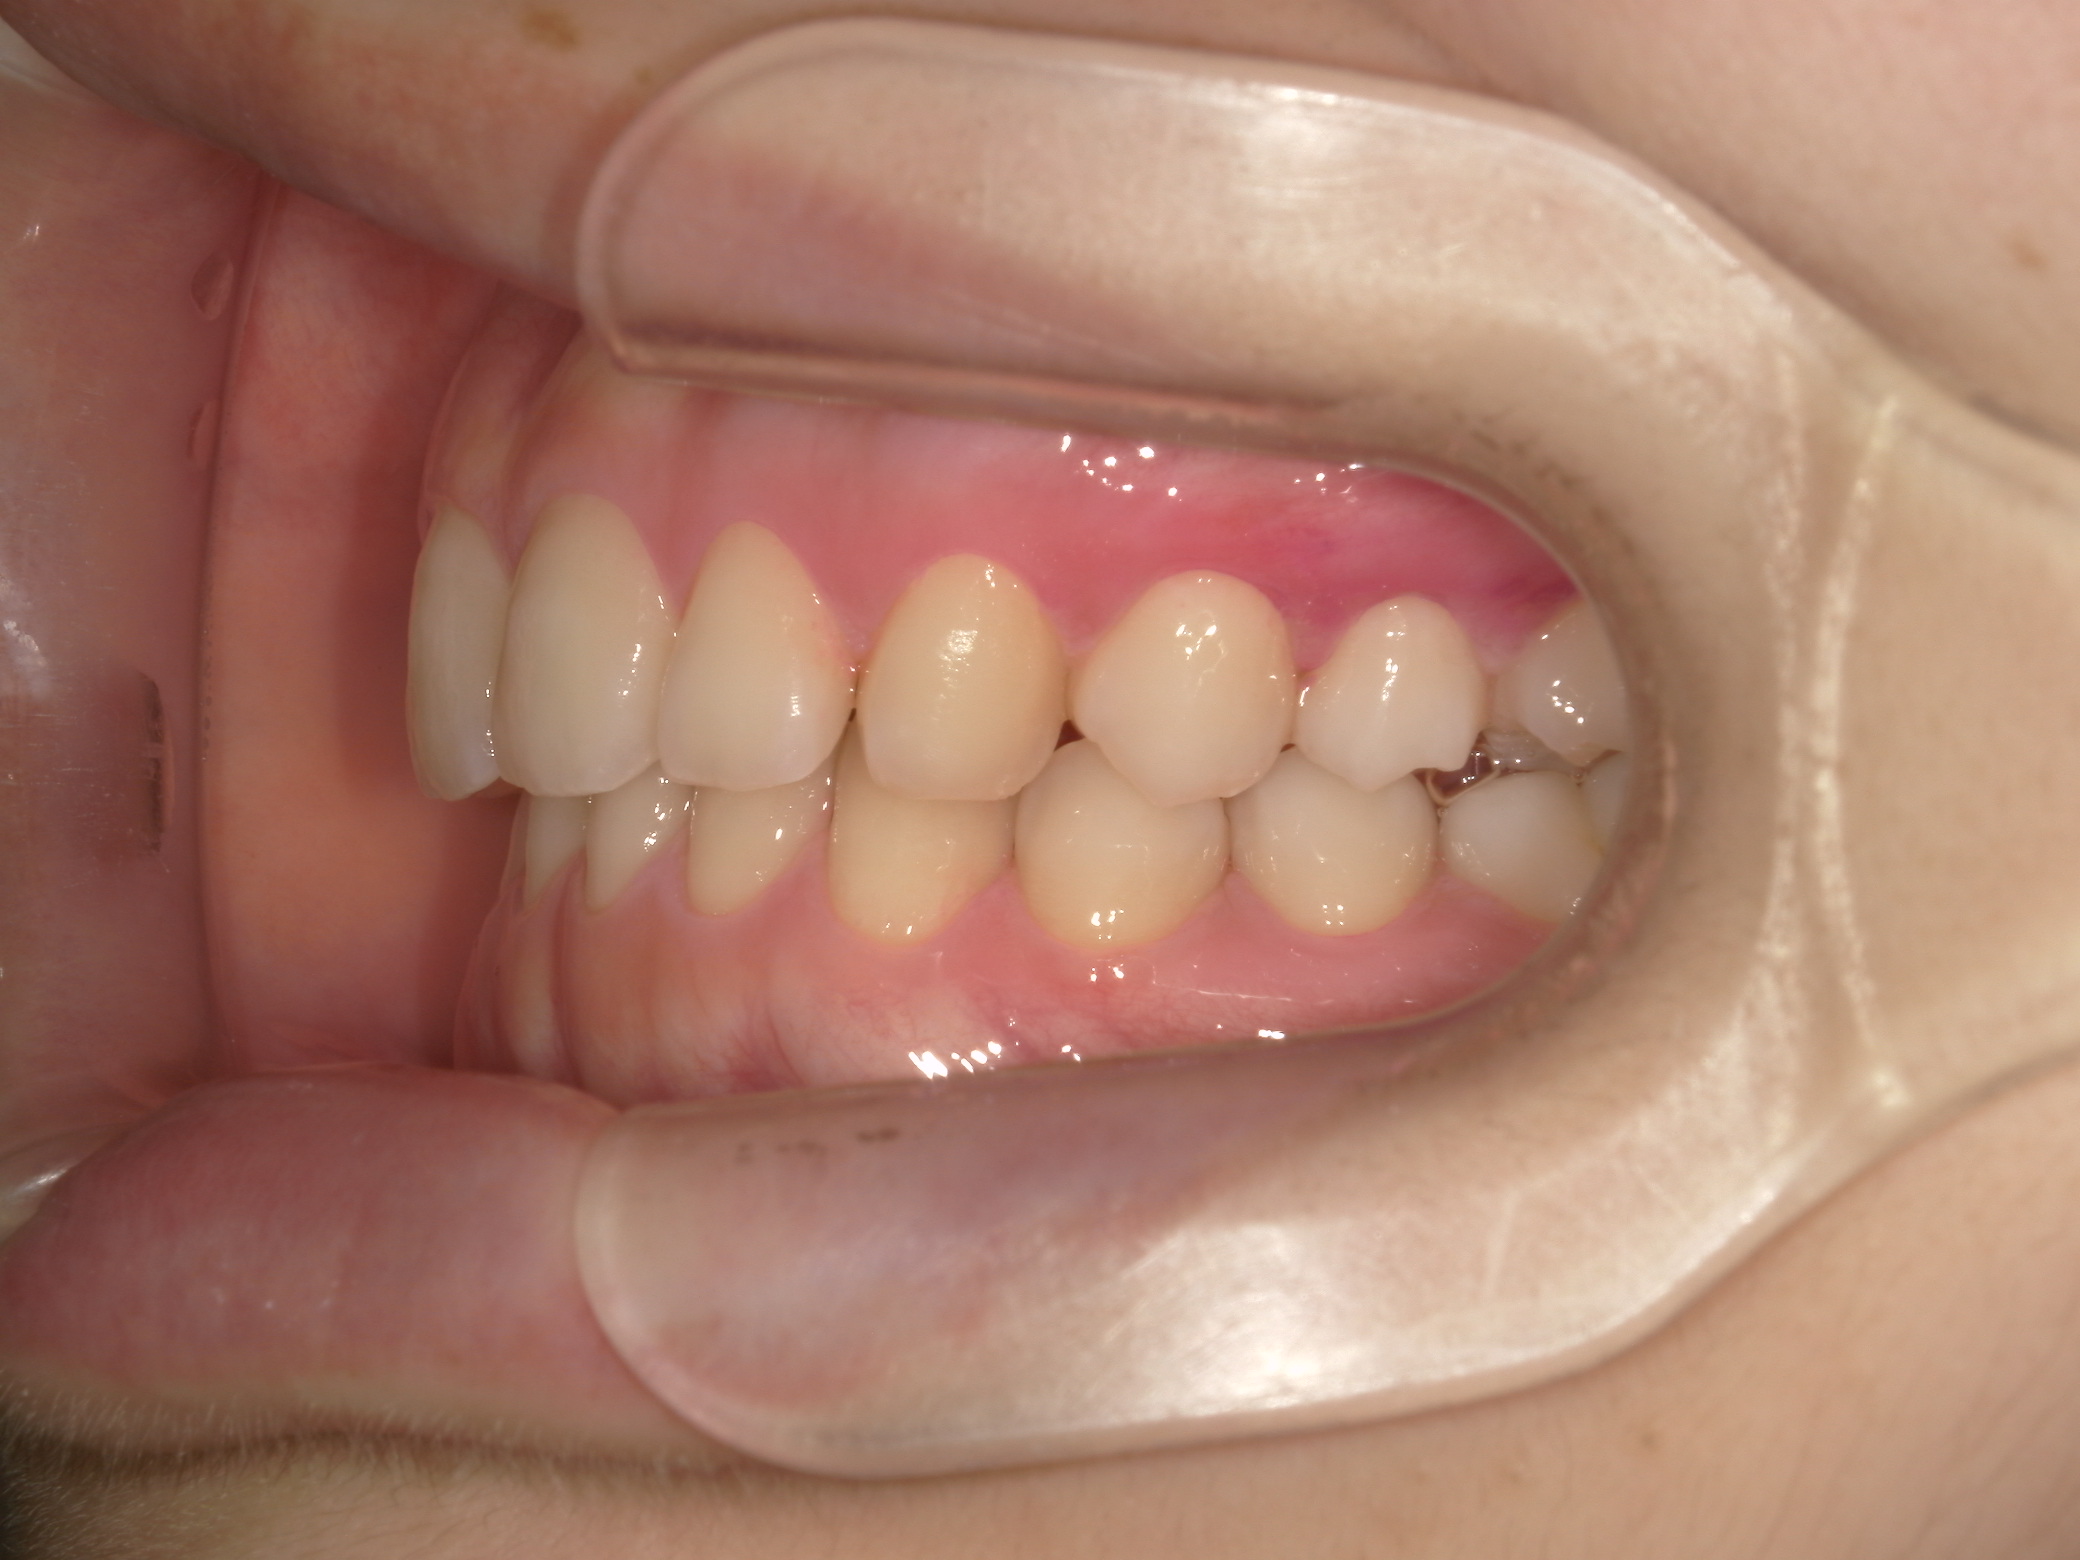

【小学生】マイオブレース矯正 上顎前突(出っ歯)と叢生(でこぼこ)を改善

小学生で開始

マイオブレース

でこぼこ

出っ歯

過蓋咬合

非抜歯

1期治療のみで改善

Before

After

治療期間

2.1年

治療開始

8歳

種類

マイオブレース矯正

使用装置

機能矯正装置

コメント

咬み合わせのズレを改善するために 矯正をされました

しっかり取り組んでくれてスムーズに終了しました